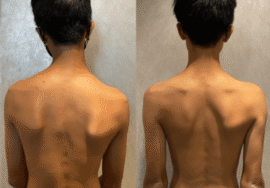

👉 وبالتالي، قد يلاحظ الأهل علامات مثل:

- عدم تساوي الكتفين

- ميلان في الجسم

- اختلاف مستوى الحوض

ومع ذلك، قد تكون بعض الحالات غير واضحة في البداية، ولذلك يتم اكتشافها متأخرًا أحيانًا.

سابعًا: ما هو Rib Hump (بروز الضلوع)؟

في بعض الحالات، قد يلاحظ الأهل بروزًا في أحد جانبي الظهر عند الانحناء للأمام.

📌 هذا يسمى Rib Hump، ويحدث بسبب دوران الفقرات وليس فقط بسبب الانحناء الجانبي.

👉 لذلك، فهو علامة مهمة على وجود اعوجاج ثلاثي الأبعاد وليس مجرد مشكلة شكلية.